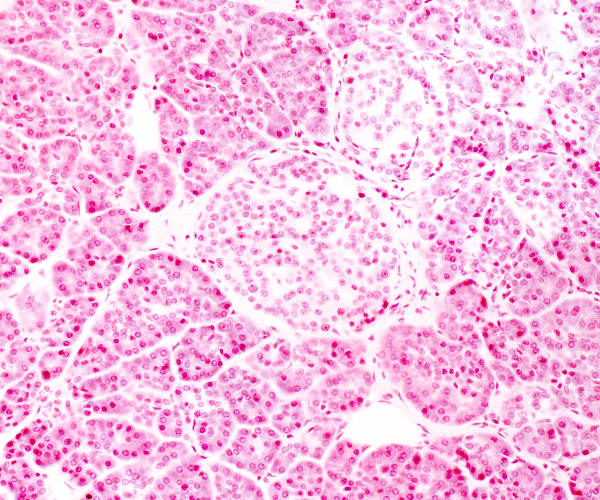

High magnification of the pancreas

© mei 2007 marius loots